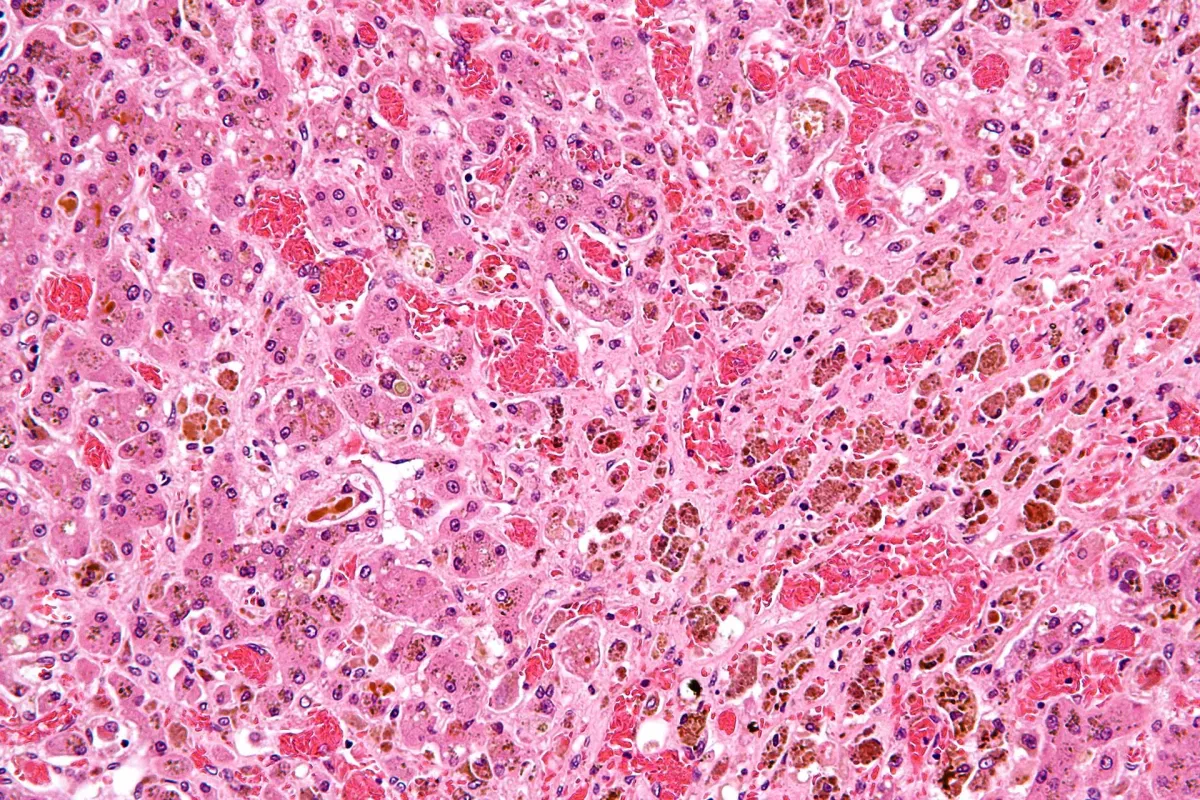

L’**excès d’alcool** et diverses pathologies affectent gravement les cellules saines du foie, appelées **hépatocytes**. Les cellules endommagées laissent un vide rempli par des **myofibroblastes**, qui créent un tissu cicatriciel dans le foie. Comme la régénération des hépatocytes n’est pas assez rapide pour contrer ce tissu cicatriciel, le foie commence à faiblir.

Holger Willenbring, de l’**Université de Californie à San Francisco**, et son équipe ont utilisé des **facteurs de transcription**, des régulateurs génétiques, pour transformer les myofibroblastes en hépatocytes.

Mais comment envoyer ces facteurs de transcription dans un foie malade ? C’est là qu’intervient le virus ! Un **virus adéno-associé** (AAV), apparenté à celui du rhume, a été utilisé pour transporter ces facteurs de transcription. Les chercheurs ont infecté les myofibroblastes présents dans le foie endommagé de souris. Une fois le virus à l’intérieur des cellules myofibroblastiques, il entame leur transformation en cellules saines.

Les résultats de cette expérimentation ont montré une augmentation significative du nombre de cellules saines et du contenu en **collagène** dans le foie des souris.